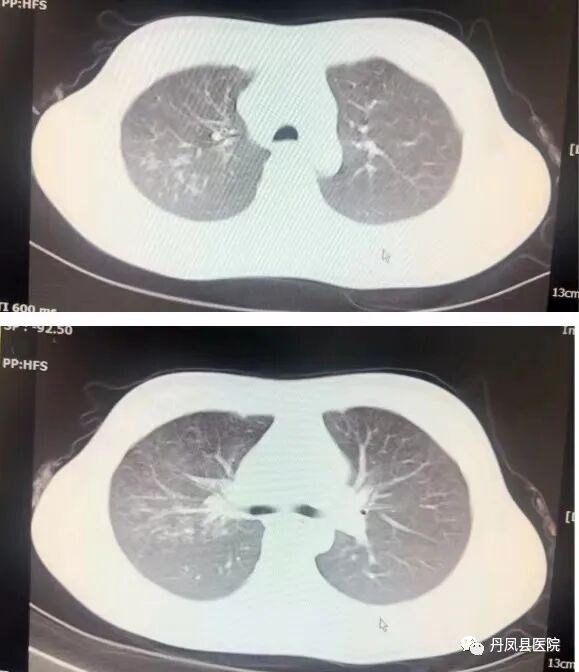

患儿男,6岁。以“发热6天,咳嗽3天”人院。患儿入院前6天出现发热,最高体温39.8℃,当地诊所治疗3天仍有发热,伴阵发性咳嗽,夜间最起为著,有痰不易咳出,遂来我院。入院查体:T37.3℃,PI12次/分,R26次/分 BP90/60mmHg,神志清楚,精神欠佳,咽部广泛充血,右上肺叩实音,左肺呼吸音粗,右肺呼吸音减弱,心律齐,心音有力。腹平软,肠鸣音4-5次/分,神经系统检查无明显异常。入院前检查:血常规:WBC6.06×109/L,L37.60%,M11.70%, N48.7%,RBC4.71×1012/L,HGB117g/L,PLT223×109/L,CRP7.8mg/L,hsCRP>5.0mg/L。肝肾功、血糖、电解质、心肌酶大致正常。凝血常规正常;痰培养:阴性;肺支原体gM抗体阳性;心电图示:窦性心动过速;胸部CT示:右肺中叶大叶性肺炎,两肺下叶支气管肺炎。入院诊断:支气管肺炎;肺炎支原体感染。诊疗经过:入院后给予阿奇霉素抗感染感染、溴己新化痰,布地奈德,特布他林雾化对症处理。经住院治疗13天,病情明显好转,出院后居家口服药物巩固治疗。出院2周病情完全恢复,复查CT无异常。![]()

![]()

治疗前后胸部CT对比![]()